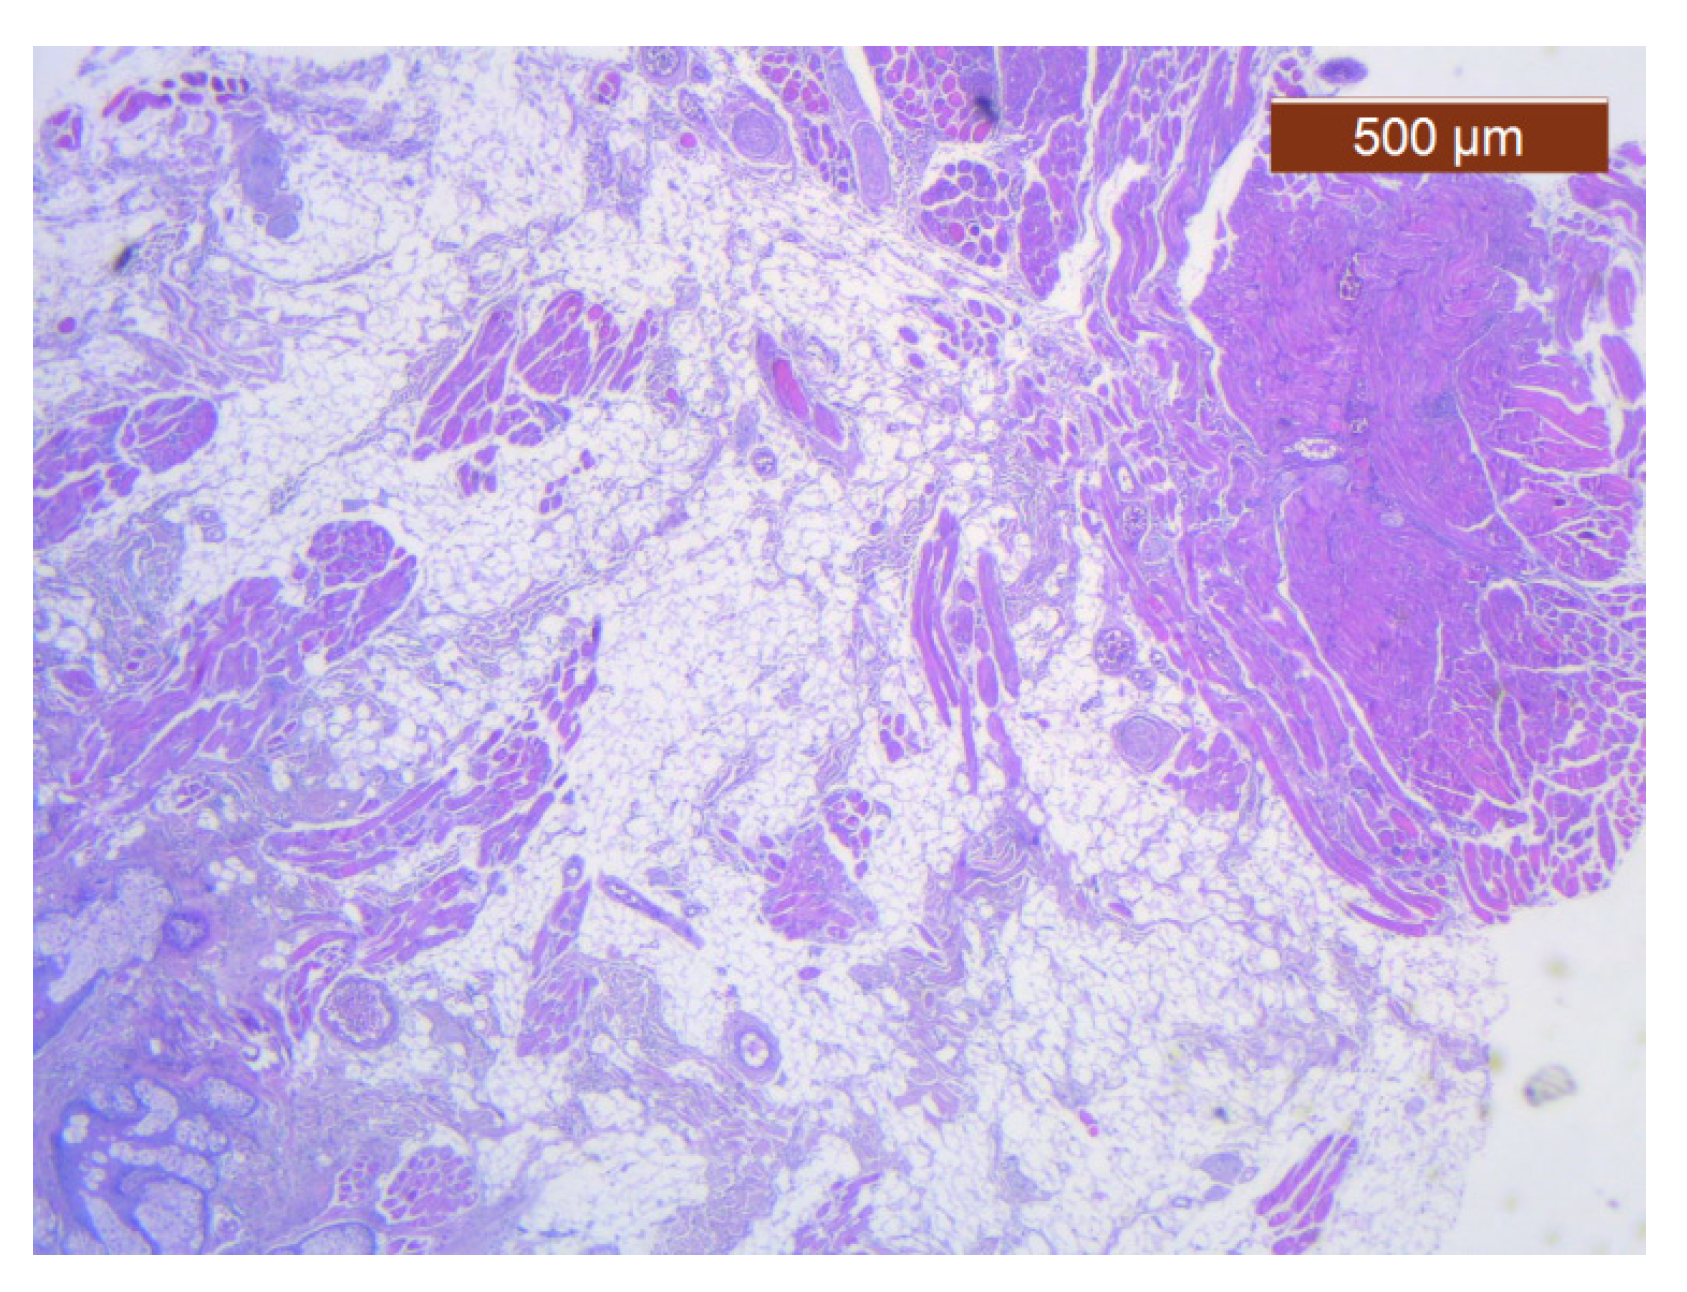

Figure 10. Subcutaneous collagen thick septa. Collagen fibers (deep), blood vessels, and fat cells (middle alar area) (HE ×5).

In this region, the arrangement of the SMAS layers from the superficial to the deep layers seemed very particular. Thus, in the immediate infradermal layer, we found strong collagen septa (Figure 10). The representation of blood vessels and muscle tissue at this level was almost absent.

Immediately below this layer follows an intermediate layer in which fat lobules are surrounded by collagen III fibers, with an apparently irregular arrangement, and blood vessels (Figure 11, Figure 12 and Figure 13). The muscle tissue is also present in this intermediate layer, but it was poorly represented (Figure 14).

Summarizing our results from this region, we can say that the SMAS is represented by a layer of fibrous skin adhesions, superficial and well represented, followed by an intermediate, transitional nutrient layer. This layer includes most of the blood vessels and lobulated macroadipose tissue, with fibers of the facial muscles of probable origin in the procerus muscle. In the deep layer, the three-dimensional collagen network from the transitional layer continues.